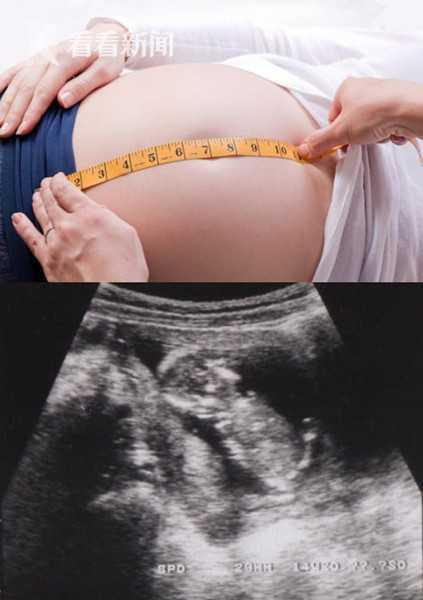

日本孕妇生产

你知道吗?在日本,孕妇生产可是件大事儿呢!从孕期保健到分娩过程,再到产后恢复,日本孕妇们可是享受着全方位的关爱哦。今天,就让我带你一起走进日本孕妇生产的奇妙世界,看看她们是如何度过这段特殊时期的吧!孕期保健:全方位呵护,只为宝宝健康在日本,孕妇从怀孕初期就开始接受全方位的孕期保健。首先,孕妇们会定期去医院进行产检,医生会根据孕妇的体质和胎儿的发育情况,制定个性化的孕期保健方案。孕期营养:日本孕妇非